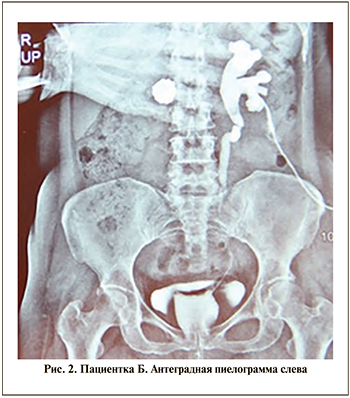

При поступлении диурез по нефростоме – 800–900 мл, естественным путем до 1 л мочи в сутки. Лабораторные показатели были в пределах нормы. Ультразвуковое исследование не выявило патологических изменений в правой почке. В левой почке толщина паренхимы составила 11 мм. В лоханке левой почки визуализировался конкремент. В нижней чашке левой почки выявлен конкремент 5 мм. При антеградной и ретроградной пиелоуретерографии – дефект в средней и нижней третях мочеточника длиной 10 см (рис. 2а, 2б).